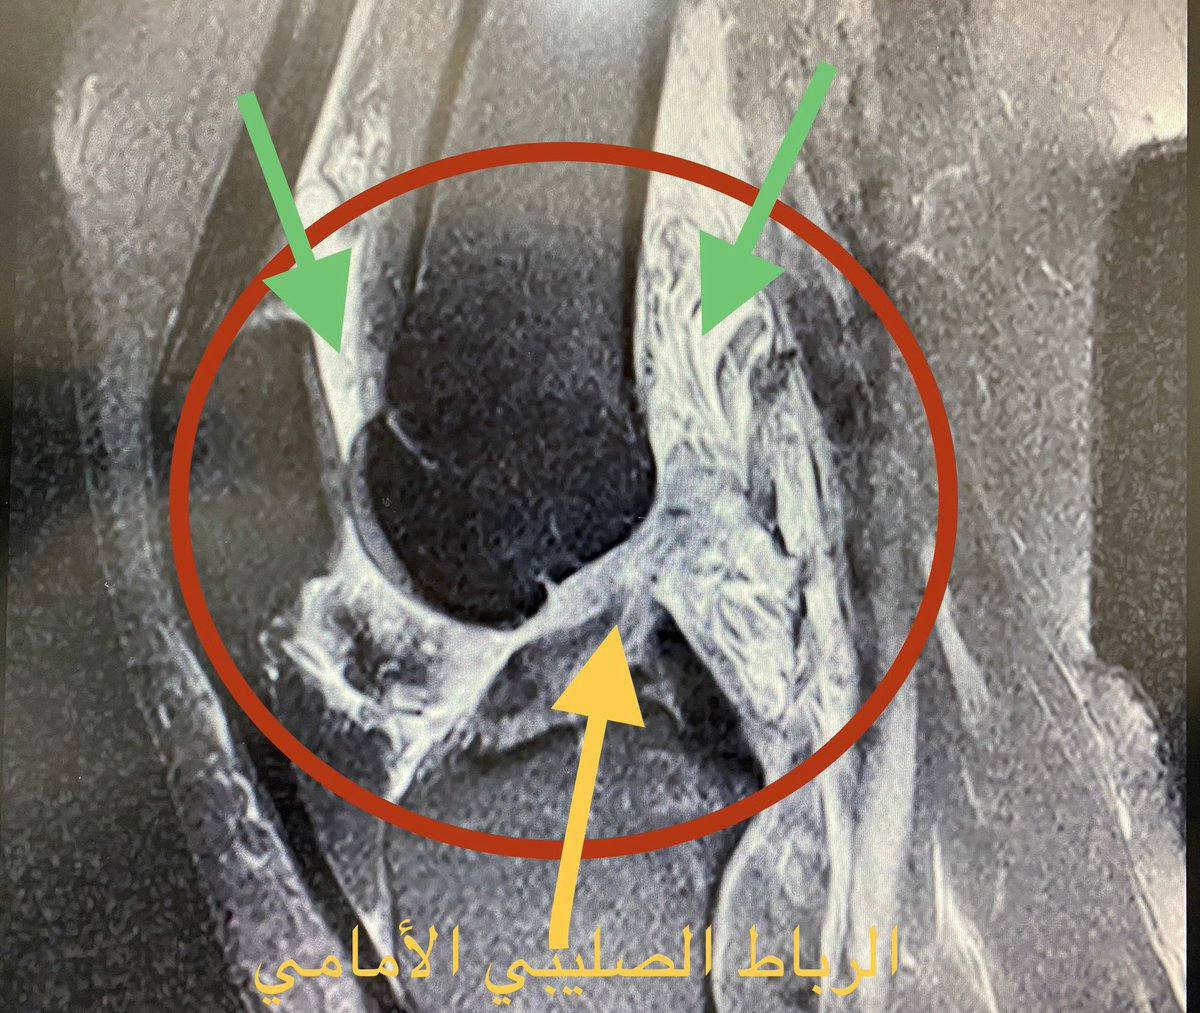

?توقيت إجراء عمليه الرباط الصليبي

أفضل وقت لإجراء عمليه الرباط الصليبي بعد الإصابه مباشره وذلك خلال ٤٨ ساعه

بعد الإصابه يحدث تورم في الركبه نتيجه تهتك الشرايين المغذيه للرباط وكذلك الأنسجه المحيطه بالركبه

قطع بالرباط+قطع بالغضروف الهلالي

اذا كان قطع الغضروف متحرك من مكانه وحركه الركبه مقفله

bucket handle tear meniscus

حيث لابد من إجراء عمليه الرباط والغضروف